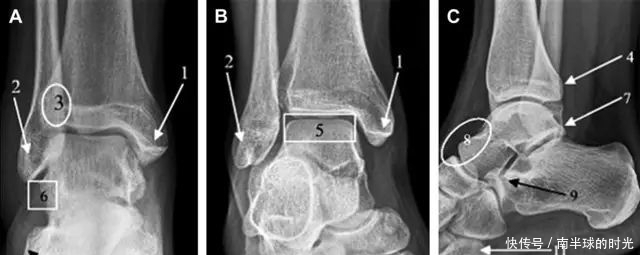

首先,来看踝关节骨折的高危区(图 1)。

图 1 踝部探查模板。阅片时,需对踝关节的前后位片(A)、内旋转位片(B)侧位片(C)仔细阅读,逐一详细排查。上图中的骨折:1. 内踝骨折,2. 外踝骨折,3. 胫骨结节骨折,4. 胫骨后踝骨折,5. 距骨骨软骨骨折,6. 距骨外侧突骨折,7. 距骨后突骨折,8. 距骨舟骨关节背侧骨折,9. 跟骨前突骨折,10. 跟骨骨折嵌插入趾短伸肌,11. 第五跖骨底骨折